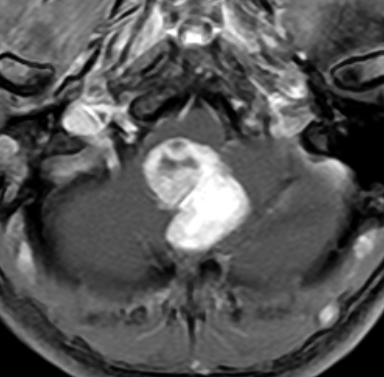

ものすごく難しい血管芽腫

これも血管芽腫です。おそらく小脳発生なのでしょうが,延髄の両側に強く癒着していて延髄の血管も腫瘍の中に入っていて,腫瘍血管には動脈瘤も合併していて破裂しました。この腫瘍を摘出するのは不可能にも思えましたが,無事にできました(下の写真)。患者さんも私もへとへとになりました。 でも,このような血管芽腫の手術はうまく行くとは限りません,手術不可能と考えた方がいいかもしれないと今でも思っています。手術すると決めればものすごく高いリスクを患者さんも外科医も背負うことになります。放射線治療をして治るサイズではないので他に治療法はありませんが (>_<) 大きな血管芽腫を手術する提案をされたら,少なくとも執刀医の経験数は尋ねましょう。